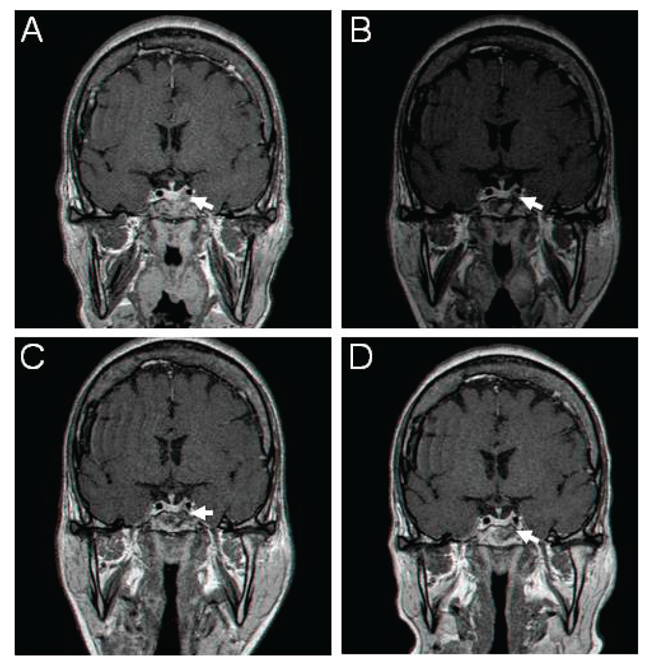

Medical therapy with a somatostatin analogue was offered within the Phase III clinical trial of long-acting pasireotide versus long-acting octreotide.10 The patient was randomized to receive octreotide 20 mg/month in August 2009. At baseline, a pituitary tumour remnant of 11×11 mm was visible by MRI in the left side of the sella, with minimal cavernous sinus invasion (Figure 1A). Her study baseline GH (mean of five consecutive measurements every 30 minutes) and IGF-1 levels were 9.5 µg/L and 96.6 nmol/L (normal, 12-24.7), respectively. After 3 months, mean GH and IGF-1 levels decreased to 3.3 µg/L and 65.1 nmol/L, respectively (Figure 2). The octreotide dose was increased to 30 mg/month, but mean GH (3.6 µg/L) and IGF-1 (63.4 nmol/L) levels remained elevated at 12 months. Tumour volume was reduced, measuring 10×4.5 mm at the end of 12 months (Figure 1B and 1C). During octreotide therapy, treatment with metformin 850 mg BID provided glycaemic control (HbA1c, 6.0-6.2%, normal, 4-5.9%).

Figure 1. Sellar gadolinium-enhanced MR images at baseline and during treatment with long-acting octreotide and pasireotide in patient 1. (A) prior to octreotide treatment; (B) after 6 months of treatment with octreotide; (C) after 12 months of treatment with octreotide; and (D) after 12 months of treatment with pasireotide. Arrows show the left-sided adenoma.

In August 2010, after 12 months the patient was switched to pasireotide, because of inadequate biochemical control as per study protocol, and was started on treatment with pasireotide 40 mg/month. After 3 months of treatment, GH and IGF-1 levels decreased to 0.8 µg/L and 9.6 nmol/L, respectively. The patient continued with the same pasireotide dose and IGF-1 levels were maintained below the lower limit of normal (LLN; Figure 2). After 12 months of pasireotide treatment, MRI revealed further tumour volume reduction (5×4.5 mm; Figure 1D). Following the initiation of pasireotide treatment, HbA1c levels increased to 7.5% after 3 months. The addition of sitagliptin (100 mg/day) and glimepiride (1 mg/day) to metformin therapy resulted in a decrease in HbA1C levels to 6.4-6.6%.